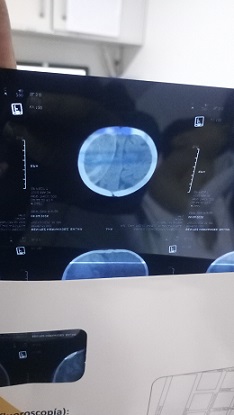

El pasado 8 de abril, el menor sufrió una caída de la cama que derivó en un hematoma subdural, una condición grave que requirió una cirugía de emergencia para drenar la sangre acumulada en su cerebro.

El procedimiento implicó intervenir su cráneo para liberar la presión, en una operación de alto riesgo que logró estabilizarlo.